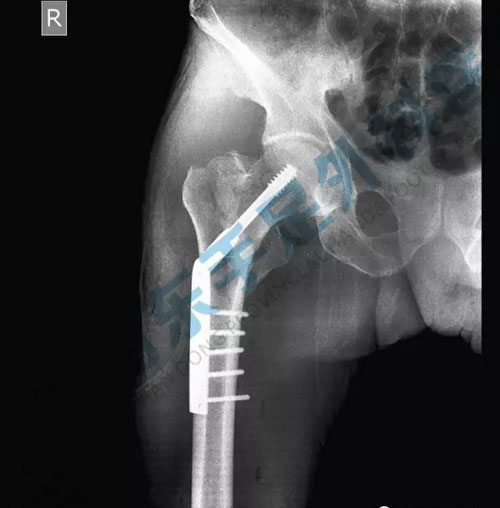

DHS术后拍片显示

相比传统手术,DHS(动力髋螺钉固定)的亮点就在于微创:切口小、术中出血少、软组织剥离少、内固定可靠、操作便捷、术后疼痛减轻以及患者可早期进行功能锻炼。